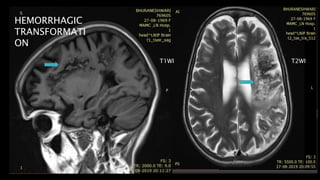

HEMORRHAGIC TRANSFORMATION (HT)

20-25% cases 2days to a week

after ictus.

Reperfusion either spontaneously or following

treatment with tPA causes exudation of blood cells

through damaged vascular endothelium and blood

brain barrier.

Petechial > lobar bleed

HT Indicates favourable outcome

HEMORRHAGIC

TRANSFORMATI

ON

T1WI T2WI

• #94 Extensive blooming is also seen within APPEARING white on phase images s/o large subacute infarct withj hemoorhagic transformation